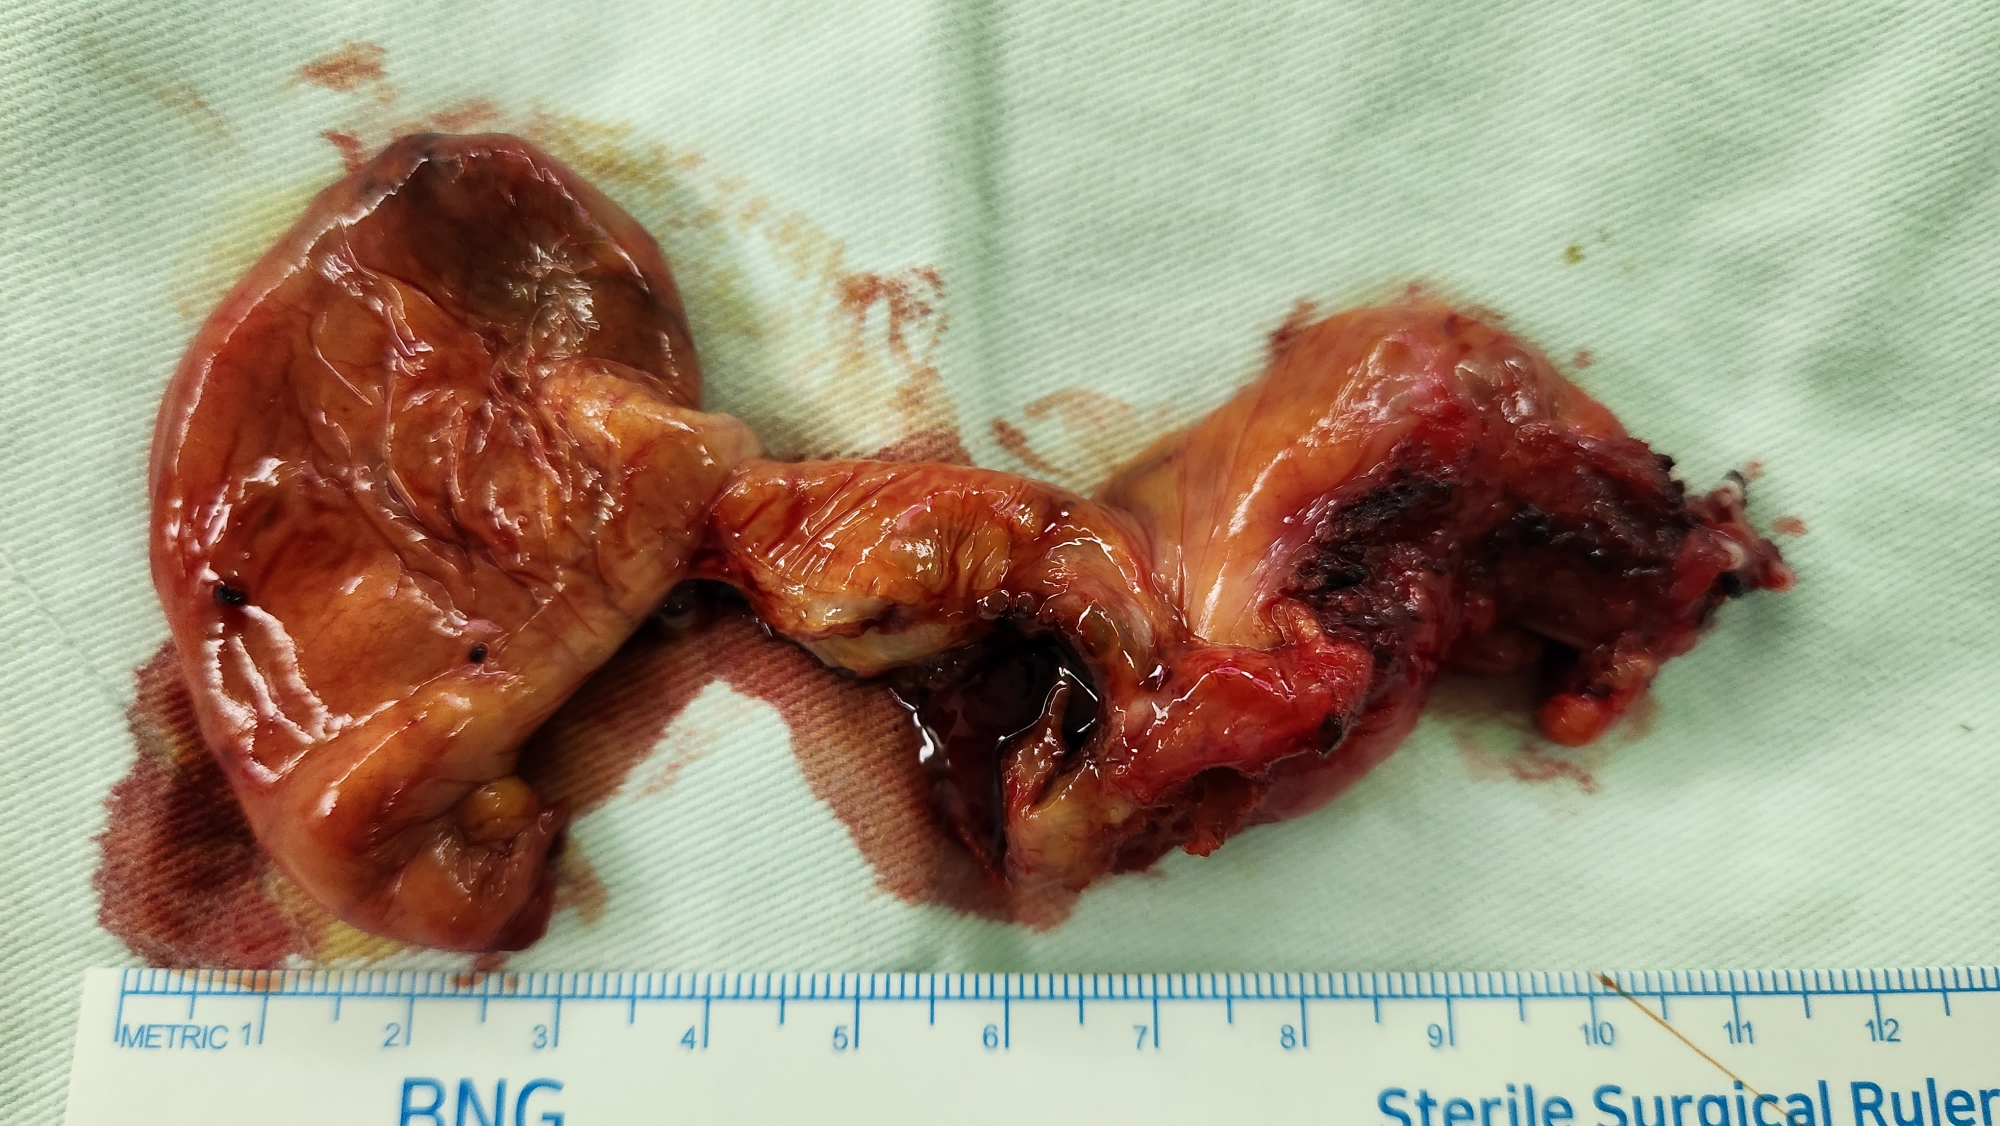

복통으로 응급실에서 복부 CT 시행후 담석 및 담낭선근증으로 확인된 분입니다.

방금 복강경 담낭절제술을 시행했습니다.

수술은 30분 걸렸습니다.